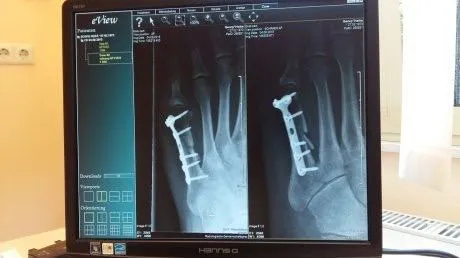

В Заречном было внедрено уникальное нововведение - рентгеновские снимки теперь печатают на обычной бумаге формата А4. Эта новость разлетелась по социальным сетям и жители Пензенской области стали обсуждать эту новаторство.

Со слов автора поста, этот шаг связан с экономией и оптимизацией процесса проведения рентгенодиагностики. Об этом ему сообщили в администрация медучреждения, утверждая, что такое изменение не влияет на качество снимков.